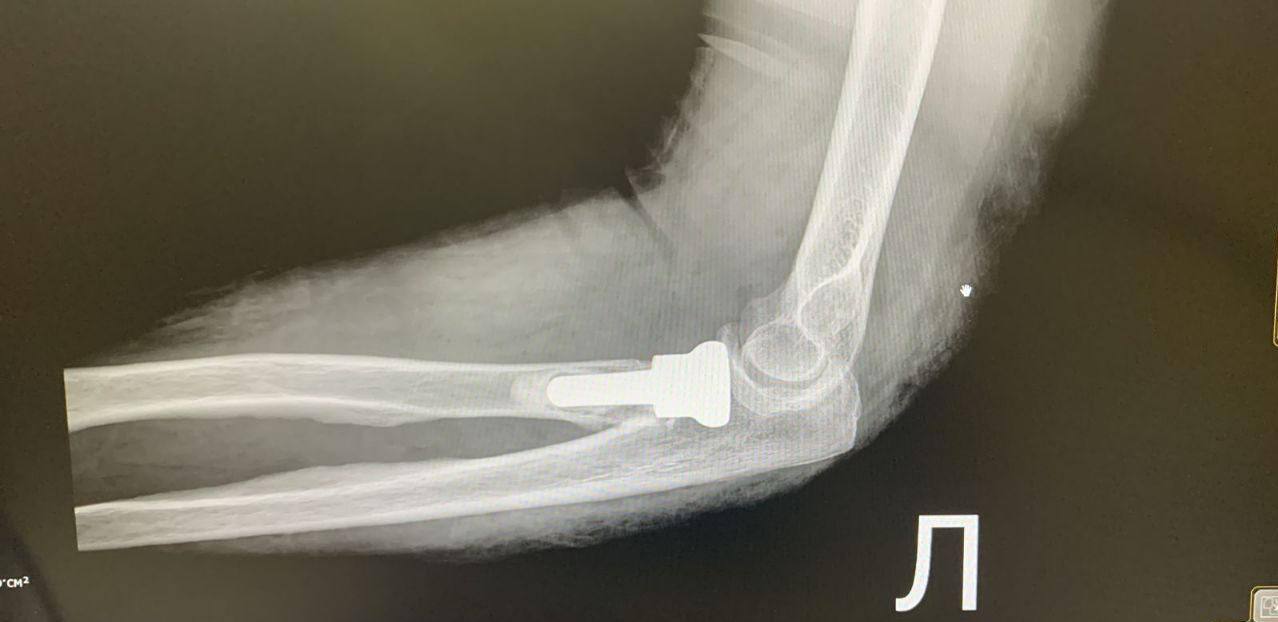

В Наро-Фоминской больнице впервые одновременно провели две сложные операции по установке эндопротезов головки лучевой кости.

66-летняя женщина и 55-летний мужчина поступили с оскольчатыми переломами, полученными при падении. Традиционный остеосинтез был невозможен — хирурги приняли решение заменить повреждённую часть кости эндопротезом.

По словам заведующего отделением, такая методика позволяет быстро вернуть подвижность локтя. Оба пациента уже дома и проходят реабилитацию.